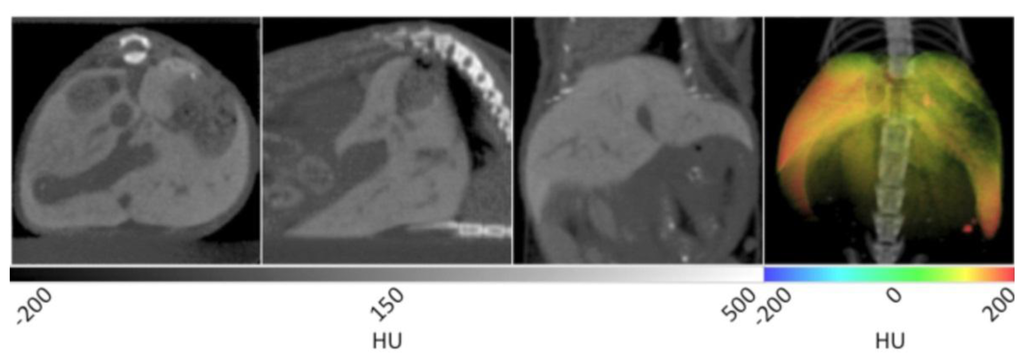

With the aid of Visipaque™ 320, renal structures are greatly enhanced during CT imaging. In Figure 6, the renal pelvis (inner core structure) is immediately distinguishable from the renal cortex (outer rim) and medulla (intermediate space in between). In the sagittal plane, the cortex can be differentiated from the medulla by its higher degree of contrast enhancement. In addition, major and minor calyxes can be identified. Although not in the same plane as the kidneys, the bladder is also readily identified using Visipaque™ enhancement. For manual segmentation, the kidneys were separated into an independent data set by drawing a VOI around them and masking the surrounding tissue. This data set was then false colored using a rainbow scale, and overlaid onto the CT to yield the 3D visualization given in the right frame of Figure 6. The gross anatomical structure and positioning of the kidneys can be observed after the original CT image is overlaid to provide spatial reference points. The highly contrast-enhanced, red regions correspond to the renal pelvises, while the medulla and cortex are noted in yellow and green. Due to the high iodine content of Visipaque™ 320, such studies can be conducted with doses as low as 30 µL without sacrificing the diagnostic abilities of the reagent.